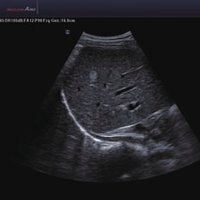

Das Samsung Accuvix A30 ist ein hochwertiges Ultraschallsystem, das mit seiner 3D-Technologie herausragende Ergebnisse ermöglicht. Das Sonographiegerät besitzt 5 Sondenanschlüsse und ist mit 20 unterschiedlichen Schallköpfen kompatibel. Mit dem A30 können Schallköpfe vom Typ Konvex, Mikrokonvex, 3D-Konvex, CW, Phased Array, Linear und Endokavitär verwendet werden. Bei zwei der Sonden handelt es sich um S-VUE Ultraschallsonden, die durch ihre höhere Bandbreite noch feinere Scans erzeugen.

6 SC1-6 Konvex 1-6 Abdomen, Fetal, Frauenheilkunde und Geburtshilfe, Niere, Notfallmedizin

8 C1-4 Konvex 1-4 Abdomen, Frauenheilkunde und Geburtshilfe, Kontrast

12 V2-6 3D Konvex 2-6 Abdomen, Frauenheilkunde und Geburtshilfe

13 V4-8 3D Konvex 4-8 Abdomen, Frauenheilkunde und Geburtshilfe